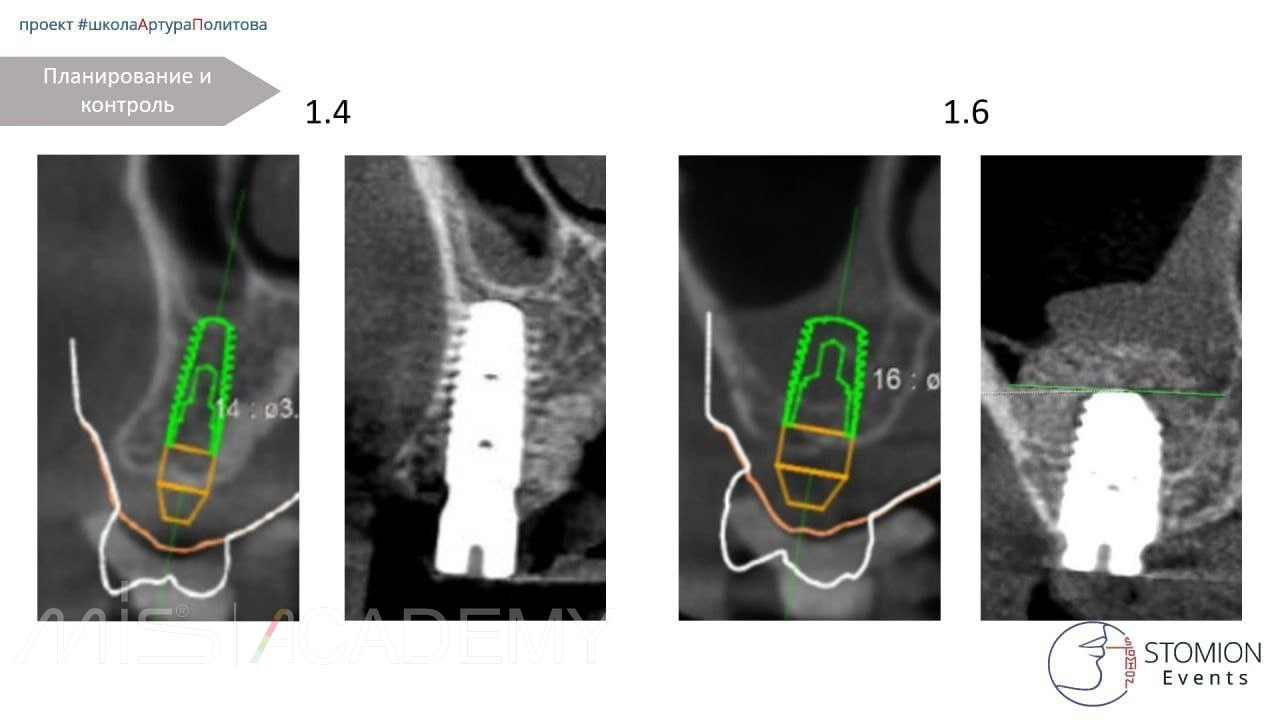

Одномоментная имплантация 2.5, 3.6, 4.6.